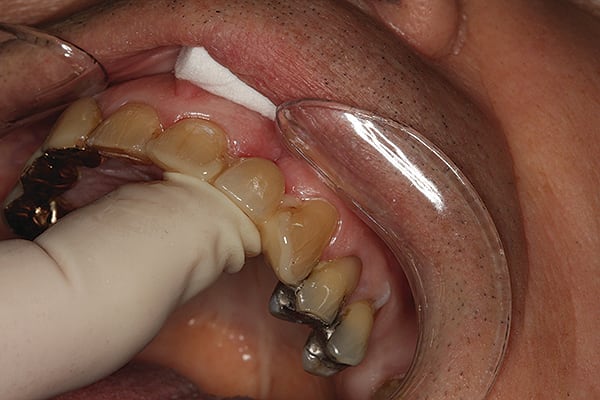

4. After successful try-in and confirmation of marginal integrity, bonding was completed and (as shown) the restoration was cleaned with 32% phosphoric acid-etch with benzalkonium chloride (BAC) (Bisco Uni-Etch w/BAC).

5. Uni-Etch w/BAC was rinsed off the restoration and dried.